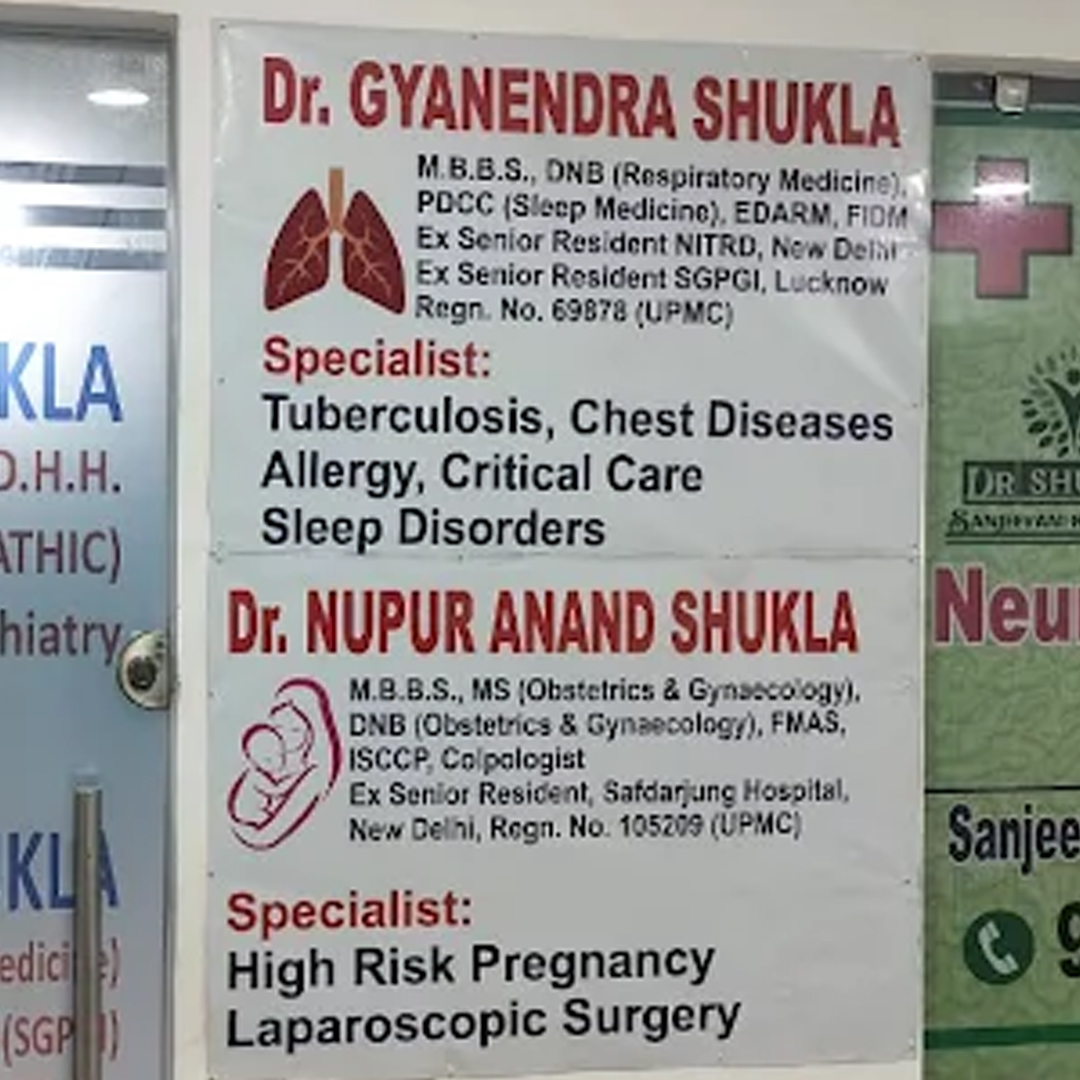

Dr. Gyanendra Shukla

M.B.B.S., DNB (Respiratory Medicine), PDCC-Sleep Medicine (SGPGI), EDARM (Switzerland), FIDM

Ex Senior Resident NITRD, New Delhi,

Ex Senior Resident SGPGI, Lucknow,

Specialist in Tuberculosis, Asthma, COPD, ILD, Pneumonia, Allergy, Bronchoscopy, Chest Diseases, Critical Care, and Sleep Disorders.